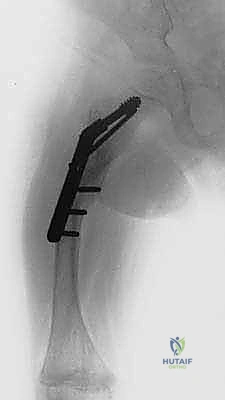

تُعد هذه العملية من أدق العمليات في جراحة عظام الأطفال، وتتطلب مهارة استثنائية كما هو الحال مع البروفيسور محمد هطيف. يتكون المسمار التلسكوبي (Fassier-Duval) من جزأين يتداخلان ببعضهما البعض (مثل التلسكوب). يتم تثبيت أحد الأطراف في أعلى العظم والطرف الآخر في أسفله. عندما ينمو العظم، ينزلق الجزء الداخلي من المسمار للخارج، مما يسمح للعظم بالنمو الطبيعي دون أن ينثني أو ينكسر.

الخطوة الرابعة: إدخال المسمار التلسكوبي

بعد تقويم العظم وجعله مستقيماً كحبات المسبحة على خيط، يتم إدخال السلك الدليلي (Guide Wire). ثم يتم إدخال الجزء الخارجي (الأنثوي) من المسمار التلسكوبي وتثبيته في الجزء العلوي من العظم (Epiphysis).

بعد ذلك، يتم إدخال الجزء الداخلي (الذكري) من المسمار عبر الجزء السفلي من العظم وتثبيته في المشاشة السفلية. هذا التصميم العبقري يضمن حماية العظم بالكامل من الداخل.